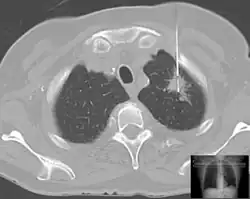

Es gibt verschiedene Formen der Gewebe- oder Probenentnahme. Meist werden Biopsien mit Spezialkanülen durchgeführt. Je nach dem verwendeten Instrument spricht man von:

Meist wird zunächst ein kleiner Hautschnitt gemacht, vor allem bei weitlumigen Biopsienadeln. Biopsien können, je nach Organ, ohne Sichtkontrolle („blind“) oder in Kombination mit bildgebenden Verfahren durchgeführt werden.